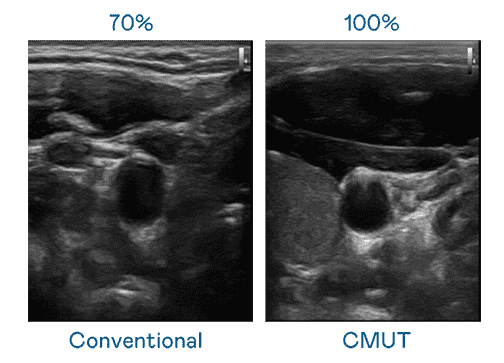

CMUT 技术是一种用电容式微机电元件来产生超音波讯号的技术。。。。与传统 PZT 压电式技术相比,,,CMUT 频宽增加 30%,,更宽频的超音波讯号让影像解析度大幅提升,,,,是实现高影像品质医疗超音波扫描、、、、促进精准医疗发展的关键技术。。。

大频宽带来超清晰影像

超音波影像的解析度高低,,,首先取决于探头能发出的讯号频宽。。。。彩霸王 CMUT 可提供高清晰的超音波讯号,,,,提供高频宽、、、高灵敏度、、、、影像纹理细节更高的超音波影像,,,,协助医护人员缩短影像判读时间及利用精准的医疗影像进行诊断。。。。